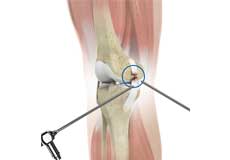

Knee Arthroscopy

Knee arthroscopy is a common surgical procedure performed using an arthroscope, a viewing instrument, to diagnose or treat a knee problem. It is a relatively safe procedure and you will usually be discharged from the hospital on the same day of surgery.

Arthroscopic Reconstruction of the Knee for Ligament Injuries

Arthroscopic knee ligament reconstruction is a surgical procedure to correct a torn knee ligament by replacing the ligament with a healthy tendon tissue using an arthroscope.